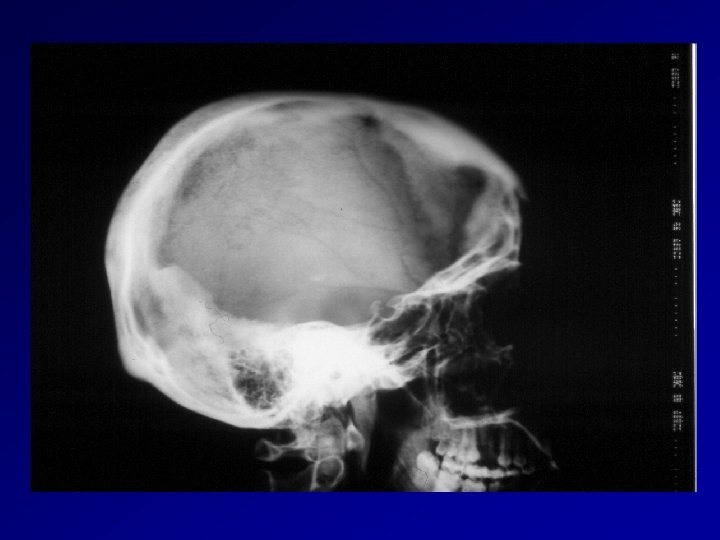

Riduzione frattura avvallata e duroplastica Frattura cranica avvallata e concomitante ematoma subdurale